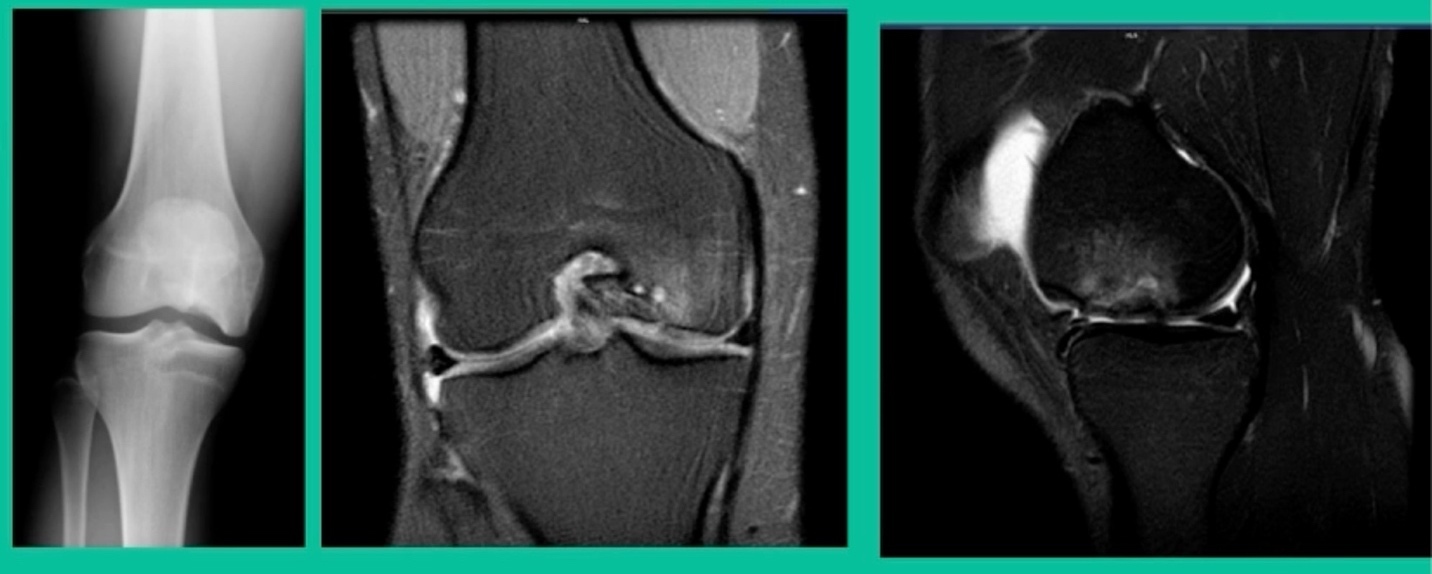

Another case example. 14-year-old male tennis player, 10 months of knee pain (Figure 7A).

This is a Trochlear defect (Figure 7B).

This goes back to metallic screw fixation, because this one is macroscopically unstable. That is a fracture non-union. That’s an atrophic non-union. Debride it, curette it, drill it, and thenwe use metal screws because it’s macroscopically unstable.

However, in this instance, we did take the screws out.

He was back to everything at 16 weeks and, at two years, he had no further symptoms. How do these do? There’s plenty of literature that shows that metallic screw fixation for unstable OCD, not just in juveniles, but in adults, will lead to reliable fixation. It’s a four-month process. They get back to everything, and they rarely have problems downstream.